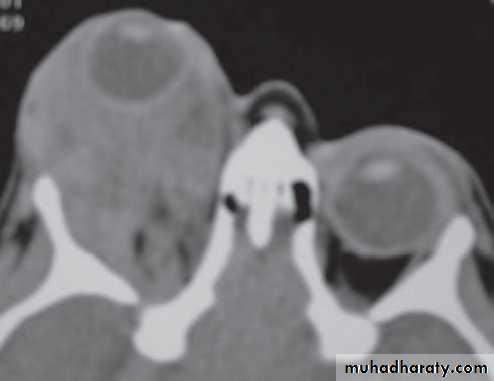

Investigation: CT and MRI show a well circumscribed oval lesion, usually within the muscle cone.

• Investigation: CT shows a round or oval mass, with a smooth outline and indentation but not destruction of the lacrimal gland fossa.